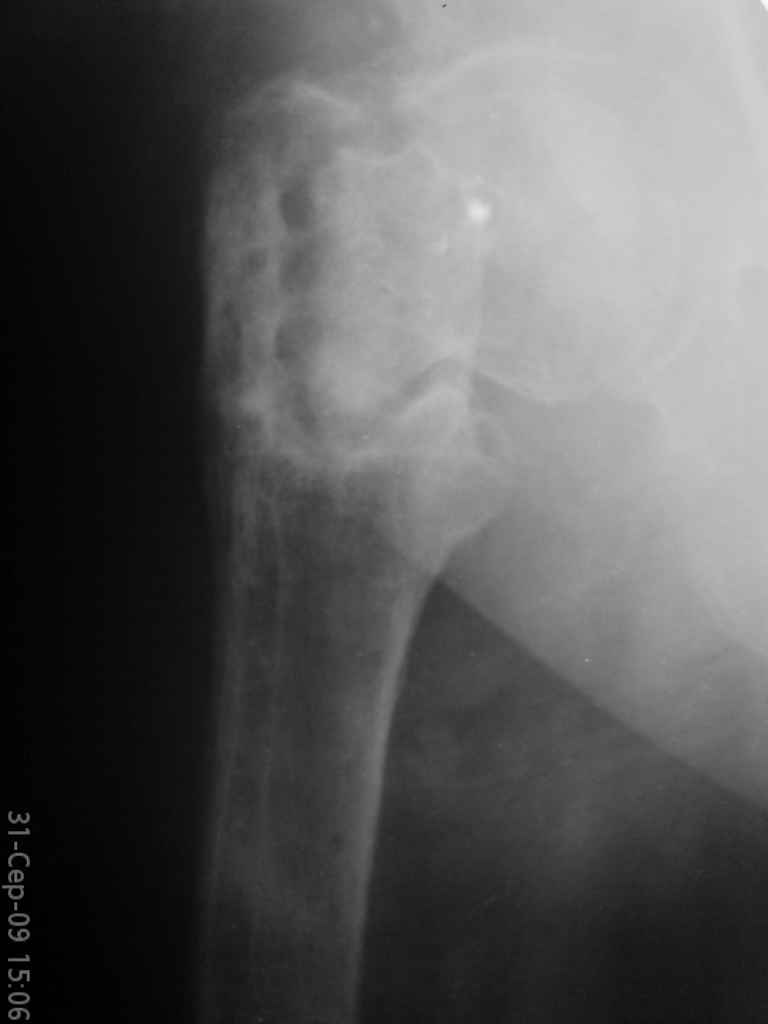

Уважаемые коллеги, помогите определиться с тактикой лечения. Больная, 62 года,жалуется на боли,неопорность левой ноги. Ходит с помощью костылей, укорочение ноги 3 см. Два года назад была оперирована кокой-то накостной пластиной, пластину удалили 4 мес назад. Вопрос такой: предлагать эндопротезирование или делать МОС (что-то по типу стержня Gamma)?За качество снимков извините, по данным МРТ - головка живая